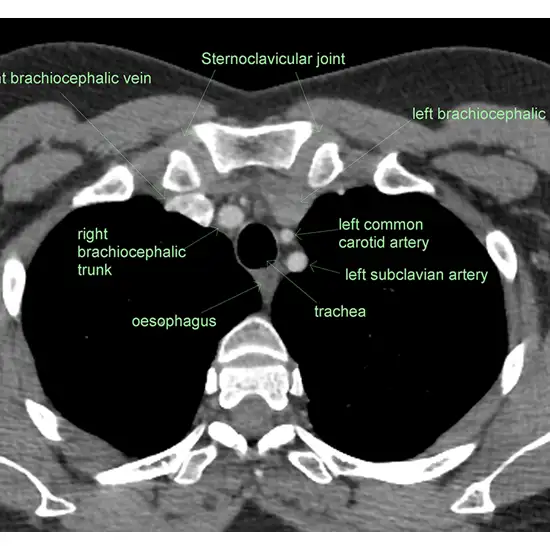

NCCT Sternoclavicular joint is a plain scan of the Sternoclavicular joint to visualise the internal organs and the disease condition in the Sternoclavicular joint. NCCT is the short form non-contrast computed tomography, this scan does not use contrast for the scanning purpose.

In this examination patient is allowed to lie supine on a table and arms are placed on the sides. The table is attached to the scanner and the table slides into the scanner for the images of the abnormal area. This scan usually takes 15 to 20 minutes.